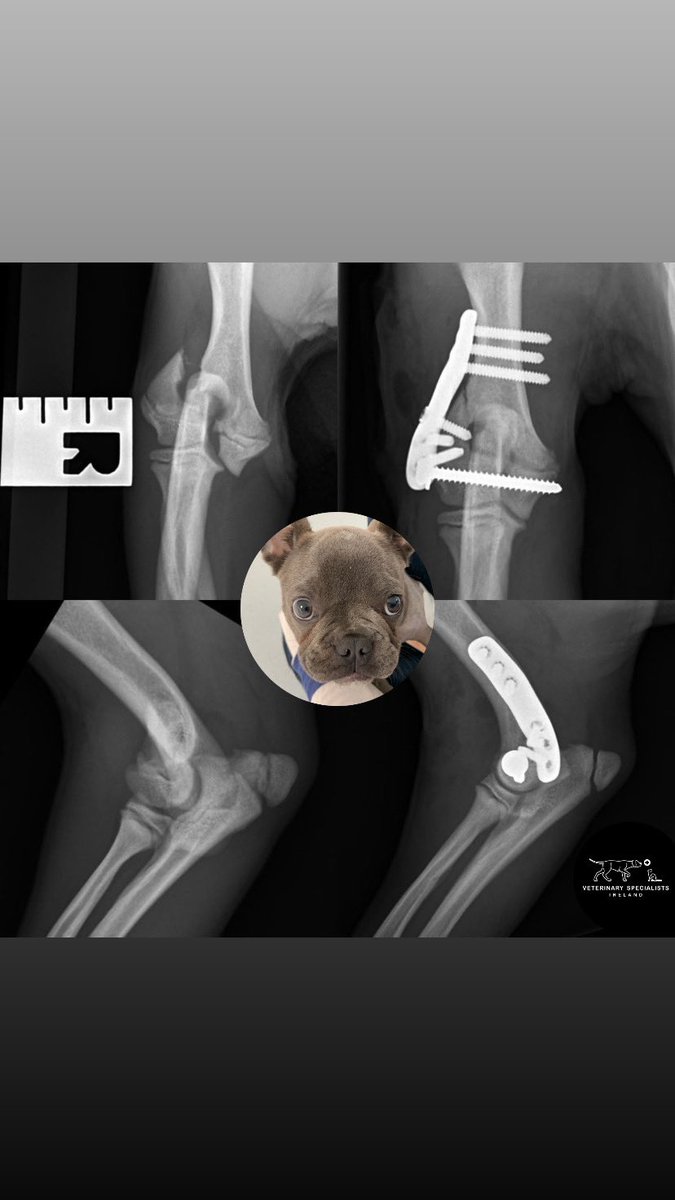

Did you know that baby Frenchies are particularly prone to elbow fractures?

Early and accurate repair is essential to restore and maintain a healthy elbow joint 💪🏻

We use custom 3D-printed implants designed specifically for French Bulldogs to optimise repair